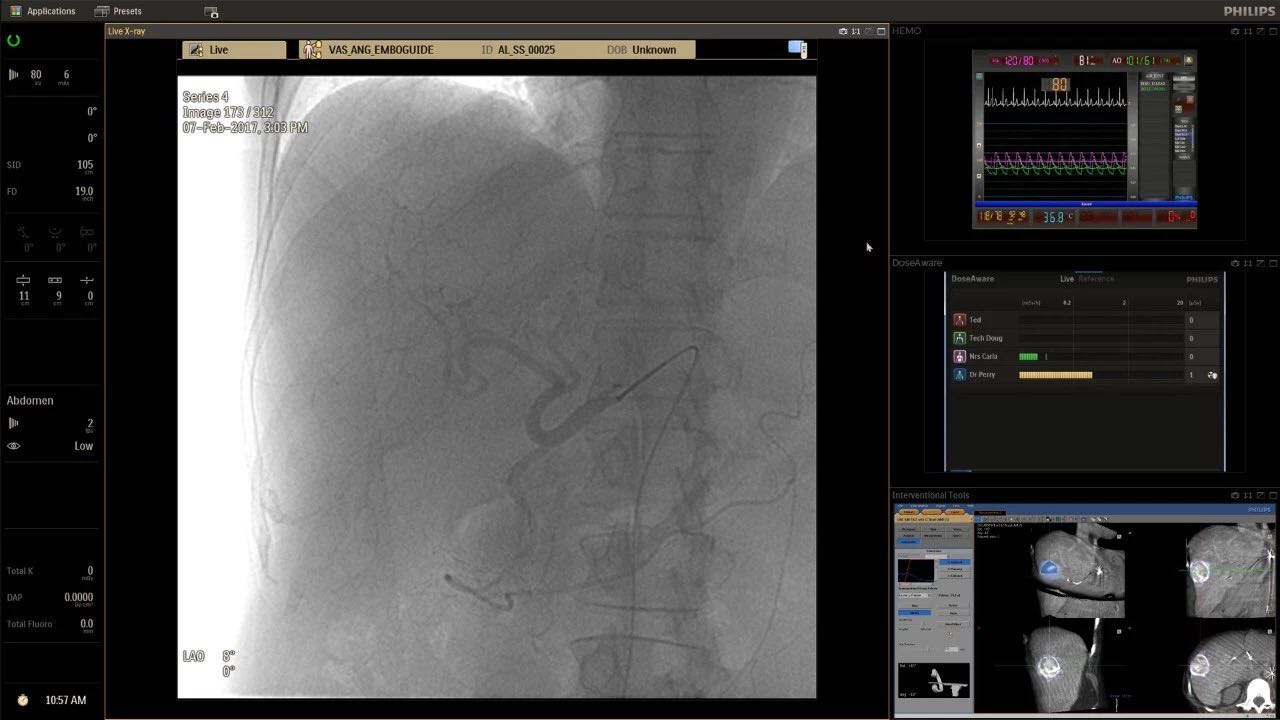

在日益復(fù)雜的干預(yù)期間,臨床醫(yī)生需要快速、輕松地可視化關(guān)鍵解剖結(jié)構(gòu)并確定手術(shù)過程中患者的變化。2019年1月17日,飛利浦宣布推出采用FlexArm的Azurion 7 C20,旨在提高圖像引導(dǎo)程序的定位靈活性。

帶有FlexArm的Azurion 7 C20 包含一系列創(chuàng)新技術(shù),使臨床醫(yī)生可以更輕松地在整個患者身上進(jìn)行二維和三維成像。當(dāng)臨床醫(yī)生移動系統(tǒng)時,圖像光束自動保持與患者的對準(zhǔn),允許更一致的可視化并使他們能夠?qū)⒆⒁饬性谥委熒稀?/span>

(FlexArm C型臂可以沿著工作臺的兩側(cè)提供偏心成像。這允許醫(yī)生在左臂或右臂上進(jìn)行徑向進(jìn)入病例,完全或部分伸展,而無需移動患者或樞轉(zhuǎn)桌子。X射線束與手臂保持對齊,以促進(jìn)其整個長度的平滑導(dǎo)航,而無需進(jìn)行持續(xù)調(diào)整。)

飛利浦表示,采用FlexArm設(shè)計(jì)的Azurion 7 C20可提供卓越的靈活性和直觀的控制。該系統(tǒng)由智能運(yùn)動引擎驅(qū)動,可在八個不同的軸上移動,所有這些軸均由其單個“Axsys”控制器控制。臨床醫(yī)生的模擬測試表明,該系統(tǒng)有可能顯著減少患者,工作人員和設(shè)備的重新定位,從而改善微創(chuàng)手術(shù)的可及性,包括通過患者手腕進(jìn)入身體的手術(shù)(橈動脈入路),并降低患者的風(fēng)險(xiǎn)。無意中拔出電線和管子,以及節(jié)省大量時間。該系統(tǒng)非常適合混合手術(shù)室(OR),可滿足一個房間內(nèi)的多種專業(yè)需求,例如手術(shù)和血管內(nèi)手術(shù)的組合。

(FlexArm在不少于8軸的情況下旋轉(zhuǎn),從而創(chuàng)建幾乎無限的靈活性來執(zhí)行成像,從頭部到腳部在左側(cè)和右側(cè)進(jìn)行2D和3D可視化。圖像光束保持與患者對齊,允許在旋轉(zhuǎn)或角度期間更好地可視化解剖結(jié)構(gòu)。使用Axsys運(yùn)動控制系統(tǒng)輕松操作支架。)